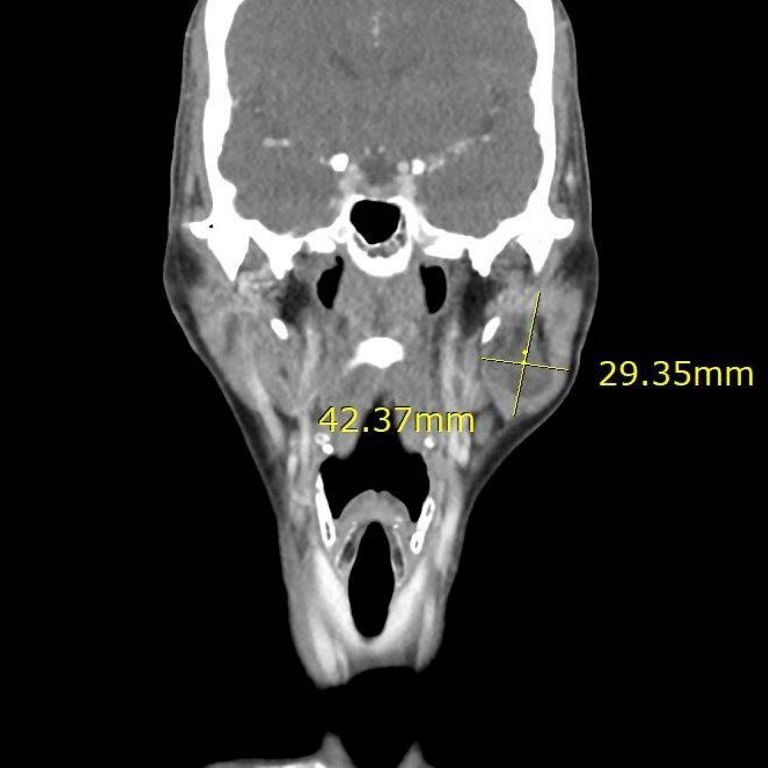

56歲的陳女士兩年前突然發現左側臉頰有約4公分的突起腫塊,這讓她變得沒有自信,生活品質也受到影響。她曾在網路上反覆查詢相關資料,擔心接受手術後臉部外觀會留下明顯凹陷,因此遲遲不敢就醫。後來決定在他院接受抽吸檢查,亦無進一步治療診斷,輾轉來到台北慈濟醫院。耳鼻喉科蔡祐任醫師利用抽吸及影像學檢查發現為腮腺腫瘤,考量外觀影響及腫瘤有惡性可能,遂透過腮腺切除手術,取出腫瘤及腮腺並利用頸部旋轉皮瓣進行修補。術後最終病理報告確診為腮腺癌中的腺細胞癌第二期,後續經放射線治療後,陳女士恢復良好,無復發傾向,且外貌不受影響,重新找回自信。

腮腺腫瘤初步可透過超音波與細針抽吸細胞檢查診斷,但最終仍需以術後病理切片判定良惡性,若診斷為癌症,除了手術之外,必要時則輔以放射線治療。過去在手術治療上,大多僅將腫塊與腮腺取出,不僅手術傷口長達10公分且病灶會有明顯凹陷,對病人外觀影響較大。因此蔡祐任醫師會同步進行旋轉皮瓣手術,首先以隱藏式傷口逐層分離腮腺組織,完整將腫瘤與周圍可能受到侵犯的組織進行切除。且由於腮腺內佈滿掌管表情動作的顏面神經,需謹慎避開,因此術中會搭配顏面神經探測器輔助定位,確保神經功能不受損害。